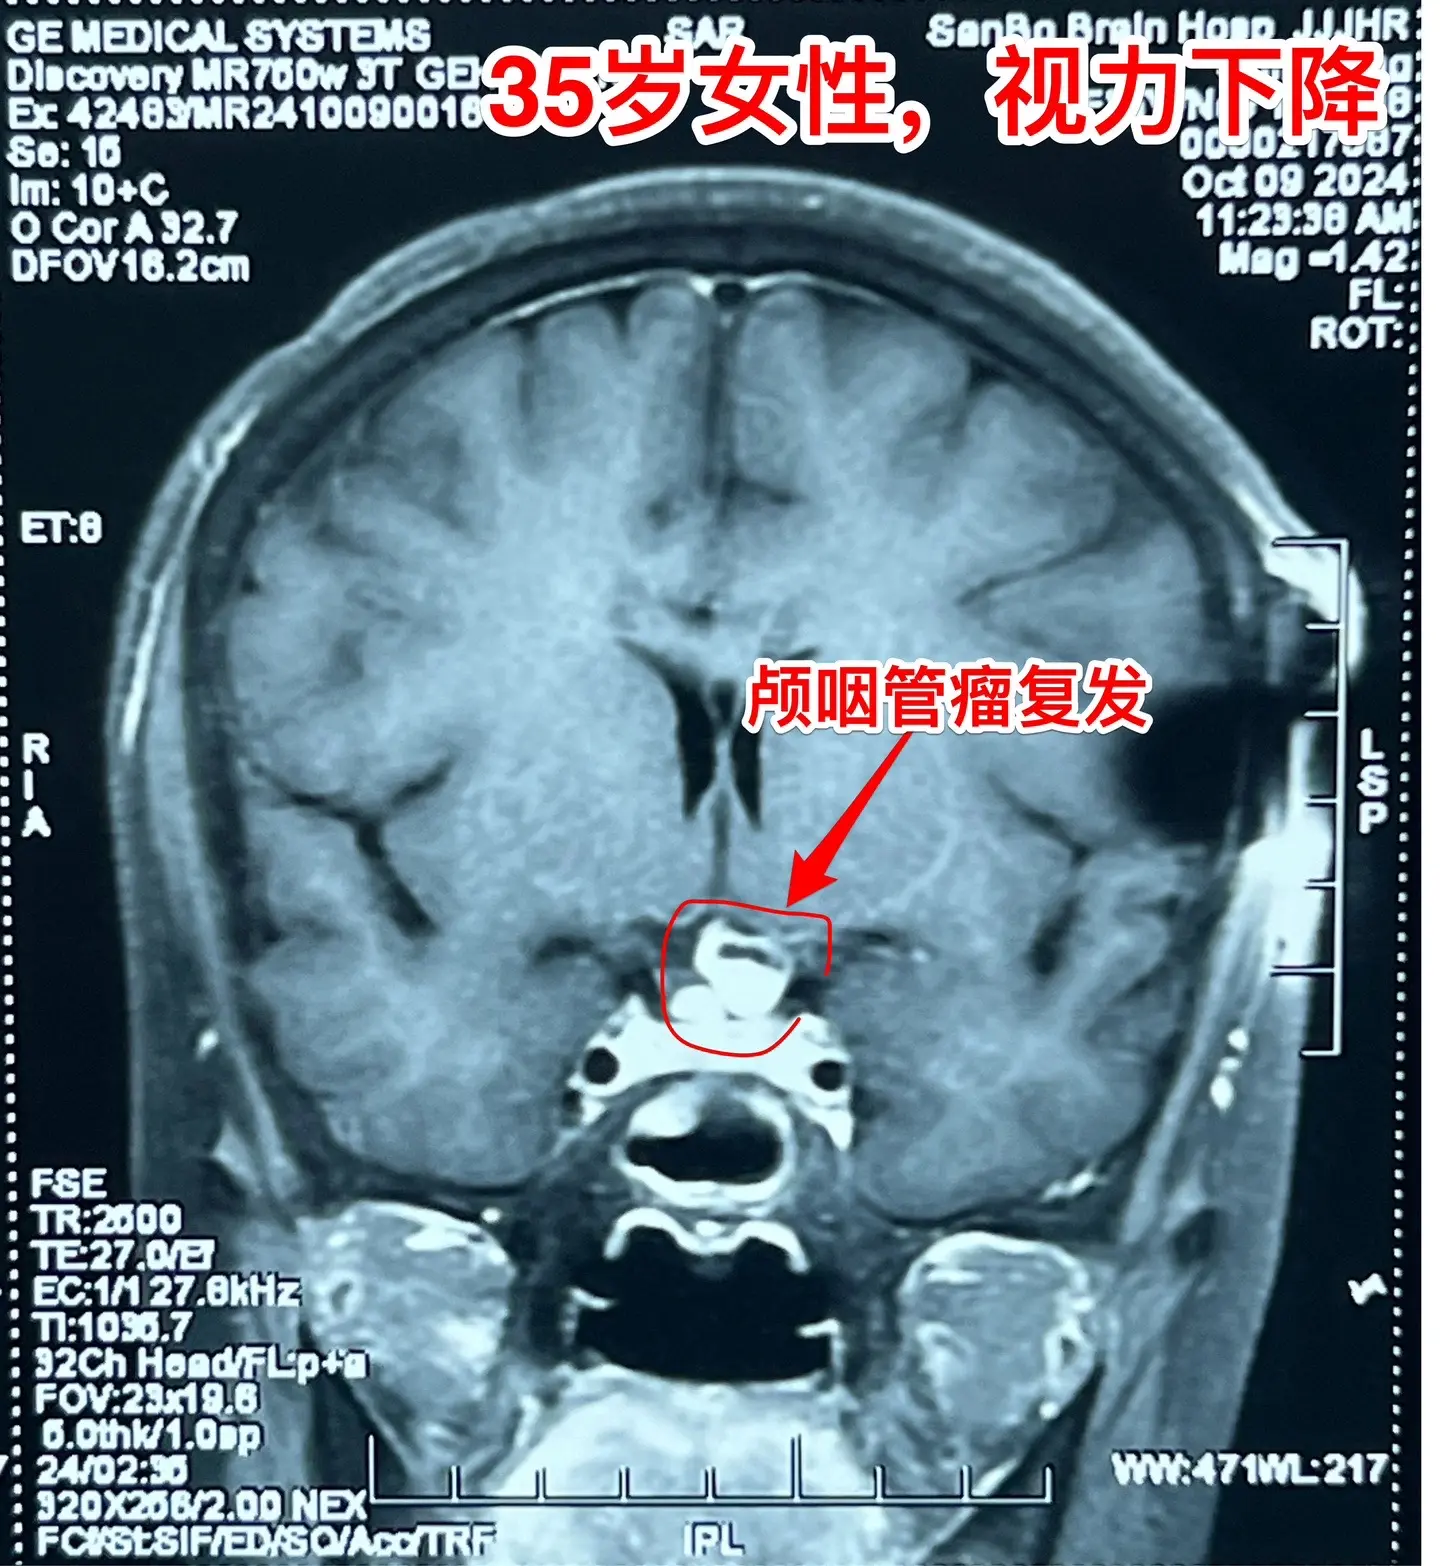

一天完成两个颅咽管瘤手术几乎成了常态。今天的两个颅咽管瘤手术,强度很大哦! 1,4岁男孩子,视力下降。典型的造釉细胞型颅咽管瘤,属于鞍隔下颅咽管瘤。开颅手术将颅咽管瘤完全切除,垂体大部分保留,垂体柄保留,下丘脑保护完好。这样的结果我们很满意! 2,35岁女性,经鼻手术后颅咽管瘤复发,视力下降。是乳头型颅咽管瘤。肿瘤与视交叉粘连很紧,手术分离难度大,最终得到完全切除。